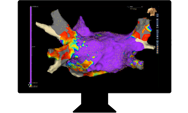

Ved hjælp af et avanceret mapping-system skaber vi et detaljeret kort over hjertet for præcist at finde det område, hvor rytmeforstyrrelsen opstår. Når området er identificeret, kan vi behandle det målrettet. Behandlingen påvirker kun de unormale celler og skader ikke det raske hjertevæv.

Hjertelægerne arbejder med en 3D-model af hjertet under ablationen. På animationen ses venstre forkammer med lungevener (de røde studser). Farverne viser kvaliteten af de elektriske signaler under proceduren, så hjertelægen kan identificere de områder, der skal behandles.